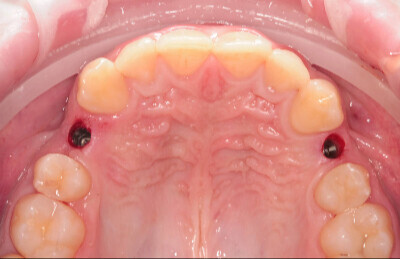

Navigovaná chirurgia, 3 implantátov

Autor práce Dr. Michal Repaši

Zubný technik Vasil Csopej